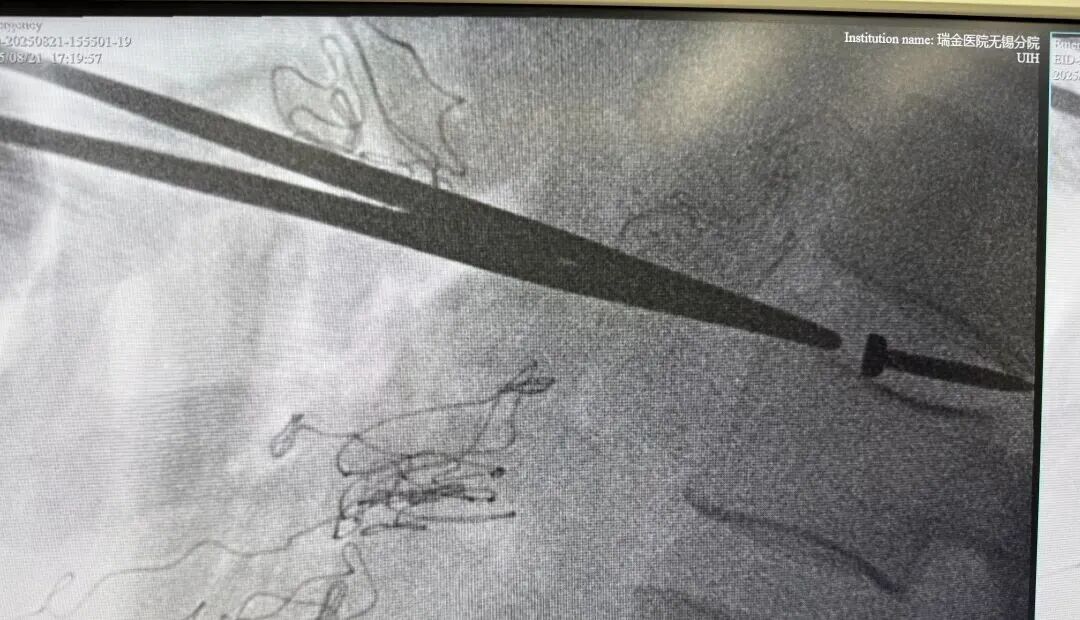

CT影像检查显示,

其腰椎间盘里卡着一枚

长约3cm的金属钉!

这根钉子从腹壁到椎间盘,

“游走”了约40cm,

疑似穿了多个腹腔脏器!

医生称,此枚金属钉依次刺穿腹壁、肝脏左叶、胃壁、结肠系膜、十二指肠、后腹膜,最终嵌插于腰椎间盘内,若处理不好很可能术后出现胆瘘、肠瘘等问题。经过3小时的手术,张师傅体内的钉子终于被取出,且取出后确认是一枚尾部有火药的工程钉

医生表示,虽然刺穿多个脏器,不过幸运的是,钉子穿过腹部时,并未伤及各大血管,并且正好钉在椎间盘之间,未伤及脊髓